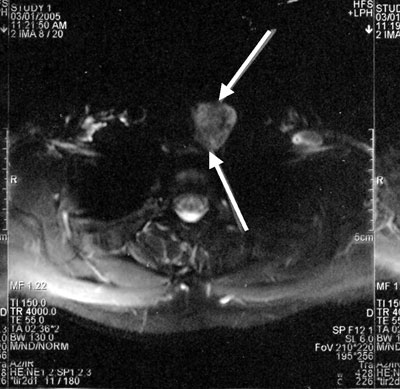

A 27-year old woman presented with a recent onset of a painless mass in the left side of her lower neck. The patient was asymptomatic and there was nothing significant in her past medical history except for iron deficiency anemia. On examination she was found to have an approximately 3 cm soft, mobile, non-tender mass in her lower neck. Thyroid function tests were normal; TSH was 1.0 mU/L (normal range 0.3-4.5), FT4 1.3 ng/dl (0.8-2), FT3 3.4 pg/ml (1.8-5). Thyroid hormones and TSH were measured by electrochemiluminescence immunoassay (ECLIA). Calcitonin, calcium, and PTH levels were normal. An ultrasound of her neck showed a multinodular goiter with 3 solid nodules on the left lobe of the thyroid, with a diameter of 1, 0.7, and 0.5 cm, respectively. A 3.4 cm solid mass of heterogeneous echotexture was identified in the left lower cervical area below the left lobe of the thyroid, separate from the thyroid, behind the sternoclidomastoid muscle with peripheral and internal flow signals. The patient refused a fine needle aspiration. An MRI scan of her neck showed a 2.5x2.2x3.5 cm well defined mass below the left lobe of the thyroid on the border between the cervix and the thorax, extending retrosternally (Figure 1, 2). The mass was suppressing the trachea but was not causing narrowing of the trachea. The mass appeared heterogeneous with hypervascularity. In the left lobe of the thyroid nodules 0.5-1 in diameter were also noted.

Figures 1 & 2. Transverse and coronal section of MRI scan of the neck showing a 2.5x2.2x3.5 cm heterogeneous mass below the left lobe of the thyroid on the border between the neck and the thorax, extending retrosternally.